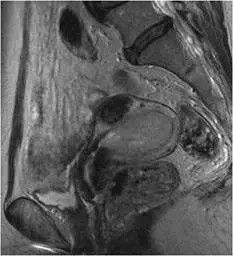

已停經的 56 歲女性病患,主訴不正常陰道出血,磁振造影檢查( T2WI )如下圖。其診斷為何?

本題為骨盆腔矢狀面(sagittal)T2WI MRI 影像,觀察要點如下:

- 子宮腔(endometrial cavity):子宮腔明顯擴張,腔內充填不均勻的中等至中高訊號(intermediate to mildly hyperintense)腫塊,訊號強度高於正常肌層(myometrium)但相對不均勻,符合子宮內膜惡性腫瘤的 T2WI 典型表現。

- 子宮肌層(myometrium):周圍肌層呈相對低訊號,與腔內腫塊形成訊號對比,可初步評估肌層侵犯深度(myometrial invasion)。

- 子宮頸(cervix):子宮頸區域結構相對完整,無明顯腫塊取代或破壞,較不支持子宮頸癌(cervical cancer)。

- 整體評估:停經後婦女,子宮腔擴張合併腔內不均勻中等訊號腫塊,臨床上高度懷疑子宮內膜癌,MRI 表現與文獻描述的子宮內膜癌 T2WI 特徵相符。